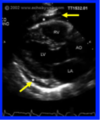

(Pic: L is normal glomerular tuft; R is lupus)

what’s seen at the longer arrows?

shorter arrows?

Long: mesangial cell proliferation

short: immune deposits -> wire loop lesions (upper left)